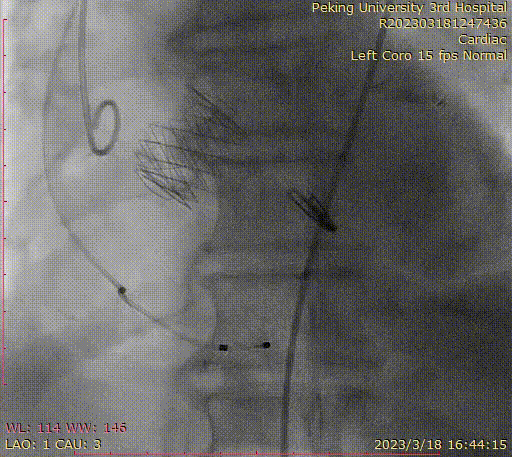

完成TAVR以及TEER后的主动脉根部造影

首先通过肋间小切口,为患者完成了左侧乳内动脉-前降支,左侧腋动脉-大隐静脉-对角支的血管吻合(MICS-CABG);随后,通过同一切口,完成了经导管主动脉瓣置换术(TAVR),最后,经过右侧股静脉途径完成经导管二尖瓣缘对缘修复(TEER)。

整个手术过程耗时6小时,没有断胸骨,没有体外循环,一站式完成三个微创手术,将患者冠脉病变,主动脉瓣病变以及二尖瓣病变全部解决。